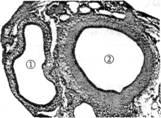

3. 图1是人体内的动脉和静脉的横切面图。图2是人体内血液与组织细胞之间的气体交换示意图。请据圈回答有关的问题。(每空1分, 共10分。)

图1                图2

(1)图1中的编号①血管是________血管,理由是该血管的管壁较________。

(2)图1中的编号②血管是________血管,血液在该血管内流动的速度________。

(5)写出血液在这三种血管之间流动的方向:(  )→(   )→(  )。